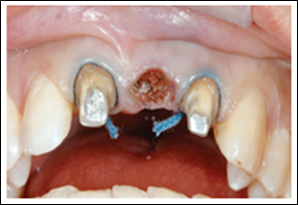

A 67-year-old man visited our office for a physical examination. The patient seemed edentulous on the upper arch, where he had a total removable prosthesis, during the clinical examination. His issue was that the denture was not stable, and he found it difficult to speak and eat.  The choice was made to put four implants in Figure 15 a. Four abutments were screwed to the implants after the surgical operation (Figure 15 a) (Figure 15 b).

Then, a bar previously constructed by the dental technician previewing the position of the implants by the maxillary arch impression was fitted in the four abutments (Figure 15 c). The bar was welded intraorally (Figure 15 d) using a dental Nd:YAG laser to secure the position. The entire intraoral welding treatment lasted 47 seconds, and the patient reported no pain or discomfort during it (Figure 15 e).

The bar was withdrawn from the mouth with the abutments (Figure 15 f), the welding technique was completed extraorally with the same device (Figure 15 g), the abutments were cut and polished, and it was then reintroduced into the mouth (Figure 15 h and i). Four silicon OT Cap (Rhein 83, Italy) were then used to secure the prosthesis to the bar (Figure 15 j). After two days, seven days, and fifteen days, the patient was evaluated again, then monthly for six months, and no concerns were found.